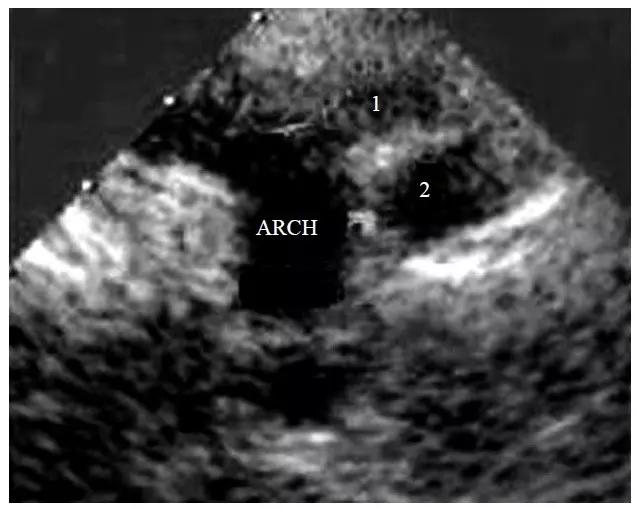

图10-6-3 B型主动脉弓离断的二维超声心动图表现

胸骨上窝切面显示主动脉弓发出无名动脉(1)和左颈总动脉(2)后完全回声中断